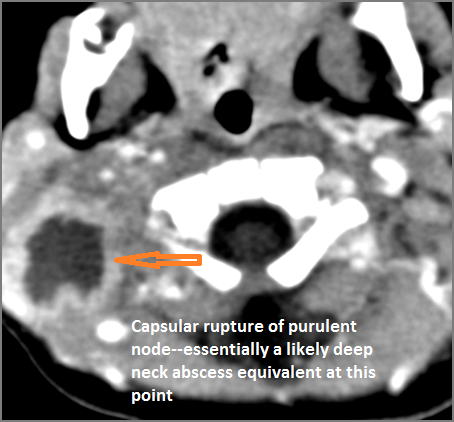

30-year old male with left facial swelling and tenderness mainly in the submandibular space. Primary clinical suspicion was an odontogenic infection.Exam

CT: Contrast- enhanced CT of the maxillofacial region and neck and related anatomy with images obtained in the balanced or venous vascular phase to ensure optimal visualization of both arterial and venous structures as well as possible reactive changes around infected collections. 0.5-3.0 mm thick sections were obtained in the axial plane and reformatted 3D and/or in the coronal and sagittal planes and viewed inter actively in 3 dimensions at the computer work station.